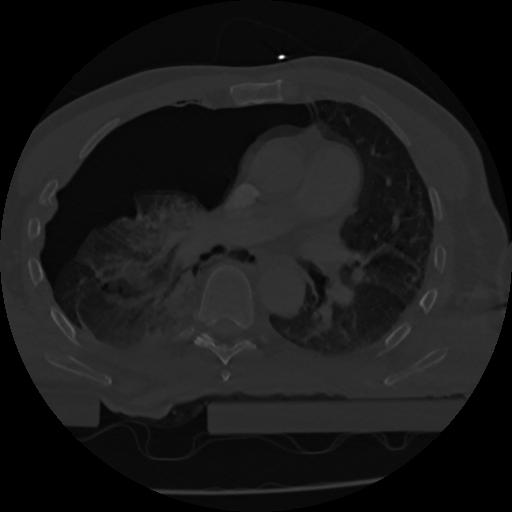

22 ANGIO,CE,Vol,0.5,ANGIO,,